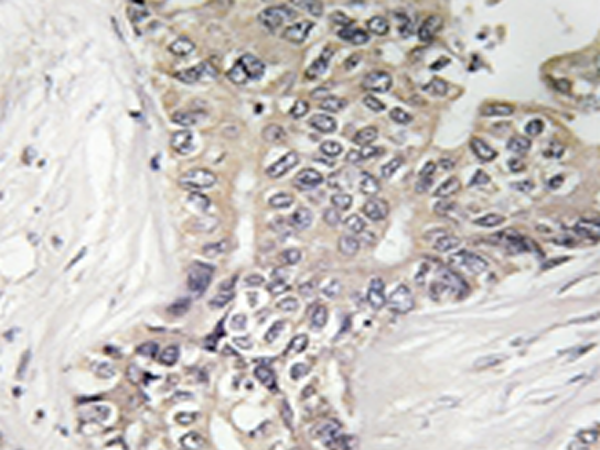

IHC positive control: |

Human liver carcinoma tissue |

IHC Recommend dilution: |

50-100 |